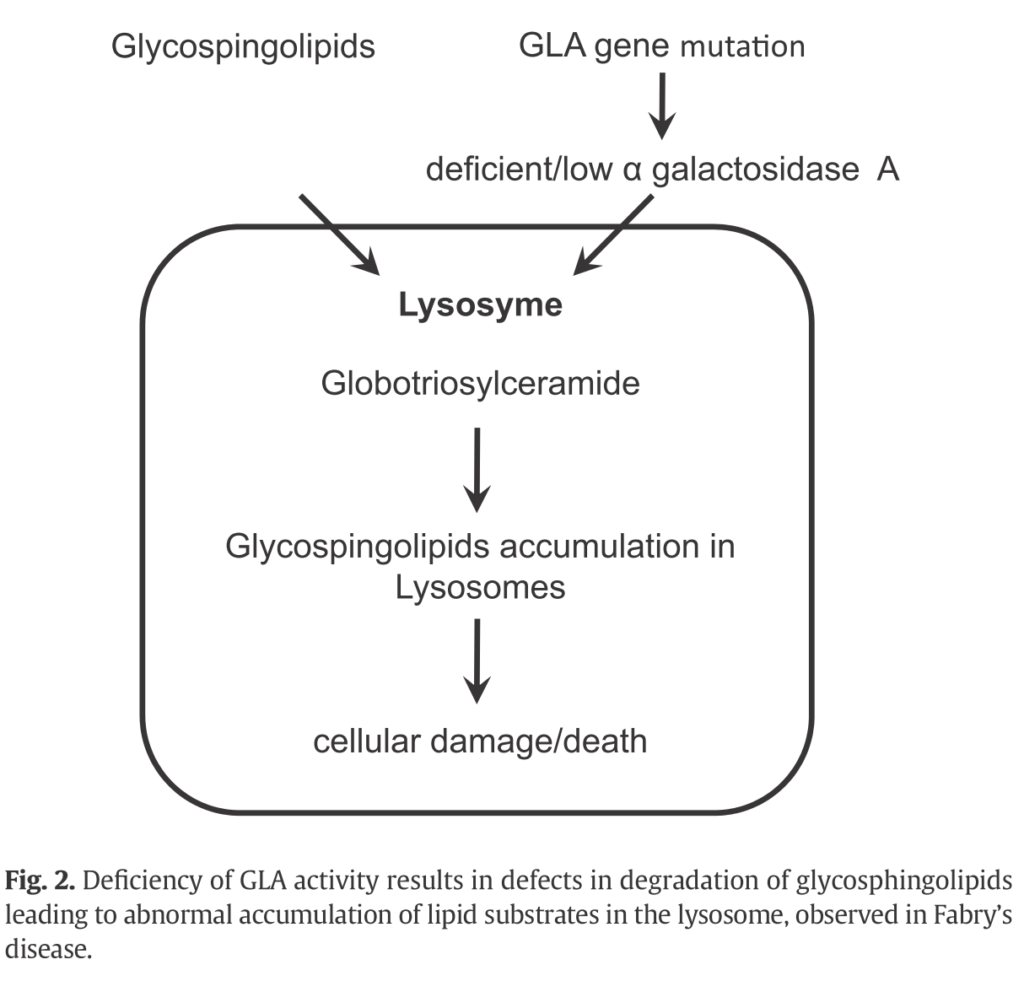

論文紹介 | 滋賀医科大学 病理学講座 疾患制御病態学部門, Fabry病│医學事始 いがくことはじめ,

Fabry病│医學事始 いがくことはじめ, 核医学(RI検査)(医療関係者の方向け) | 京都市立病院,